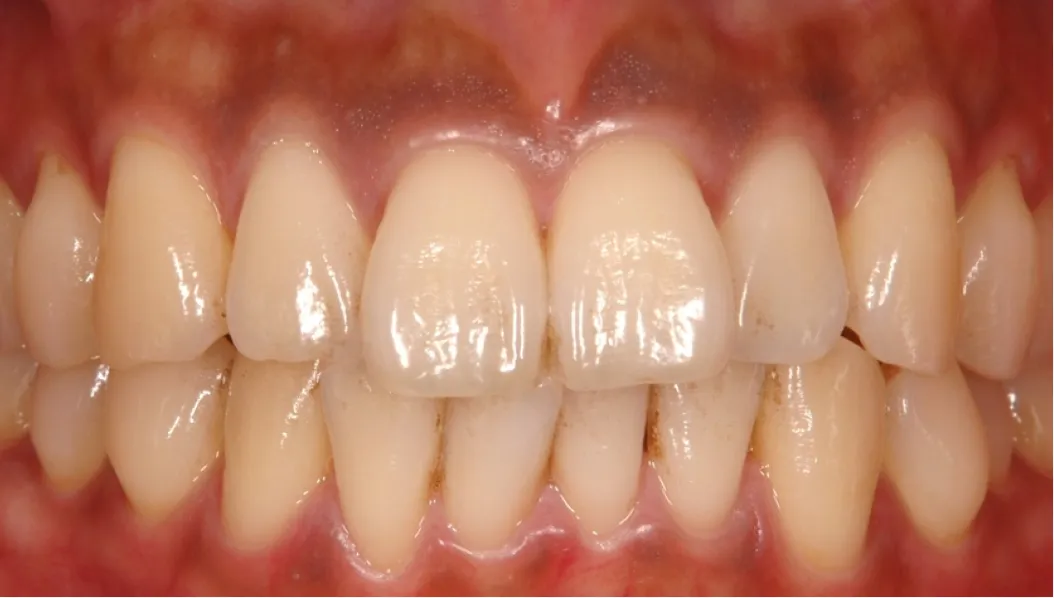

このような治療を行うことで、歯茎の黒ずみはほとんどわからなくなり、被せ物もセラミックで作り直すことで、患者様のご希望通りの自然な見た目を実現することができました。

●徹底的な歯周病治療を行い、健康的な歯茎にする

●歯ブラシがきちんと行えるような被せ物の形態にする

歯ブラシがきちんと行えるような被せ物の形態にしたことで、再び歯周病を発症することを予防し、今回の処置によって綺麗になった歯茎をより長く健康的に維持し続けられるように治療を行いました。 当院では、 その場しのぎではなく長期的に患者様のご希望を満たせるような治療を心がけております。